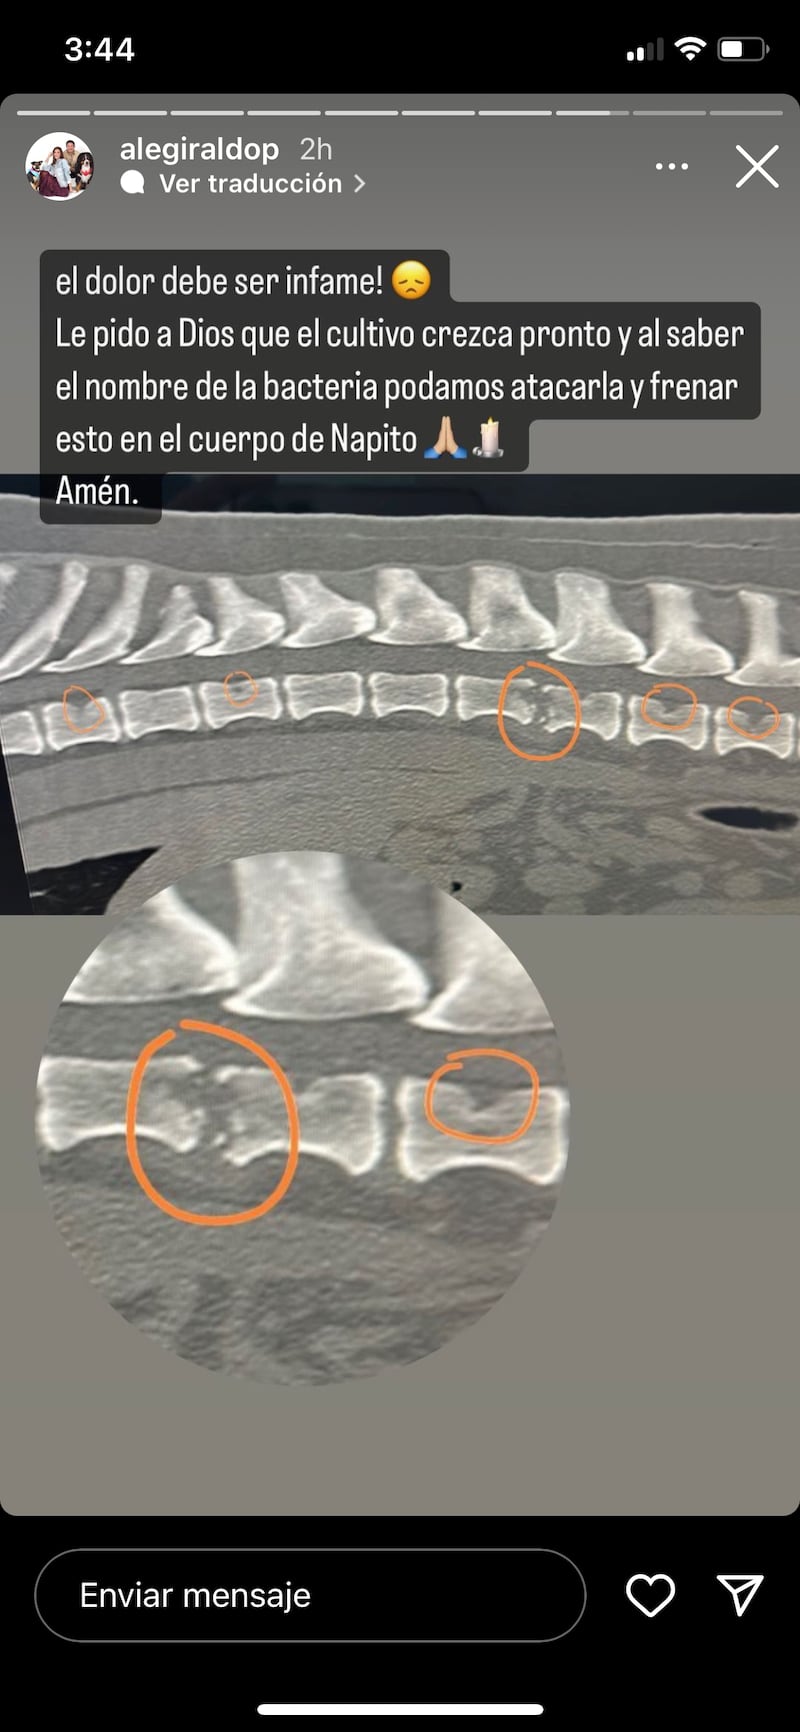

Sin embargo, esta situación no terminó allí, pues días más tarde gracias a una serie de exámenes se dieron cuenta de que ‘Napito’ tenía una bacteria era quien se estaba comiendo sus vértebras y por ende, el dolor en su columna era crónico, tanto así, que el canino lloraba del dolor, este padecimiento es mejor conocido como: espondilitis infecciosa.

Este padecimiento logró descubrirse luego de varias semanas, tras una serie de sueros, medicamentos fuertes, acupuntura, CBD, entre otros. Actualmente, ‘Napito’ se encuentra bajo algunos medicinas las cuales buscan combatir esta bacteria. Cabe resaltar que el perrito según Alejandra, siempre ha sido muy sano a pesar de la edad que tiene.